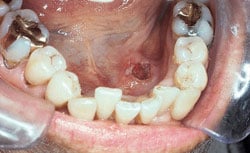

Erythroplakia

Erythroplakia (e-ryth-ro-PLAY-ki-a) is a red patch that may be found in any part of the mouth but is most common in the floor of the mouth or on the gum tissue behind the back teeth. The cause is unknown but is most likely associated with smoking or other tobacco use and alcoholic beverages. Chronic irritation and poor nutrition may also be contributing factors. Although erythroplakia is less common than leukoplakia, most of these lesions are found to be precancerous or cancerous when biopsied. Red lesions that do not heal in a week or two should be evaluated by your dentist. This applies even if you do not smoke or drink alcohol.